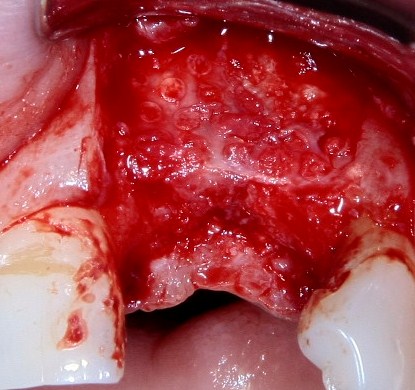

Другой вариант. Имплантируем, но существующего объема костной ткани недостаточно для получения адекватного эстетического и функционального результата:

Поэтому мы используем мембрану Geistlich BioGide и всё ту же аутокостную стружку:

Вот чем мне нравится мембрана BioGide — так это своими свойствами. Предсказуема до мелочей.

Во влажном состоянии она эластична и податлива, поэтому нет необходимости использовать пины или винты:

ну и, швы: